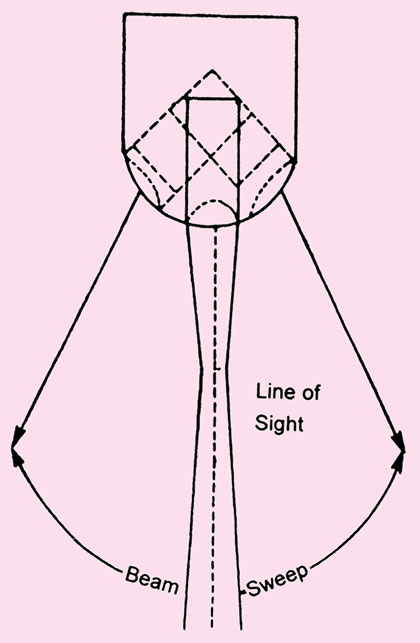

The most important classification of real time imaging system is based on the method by which ultrasound beam is swept through the regions of interest. There are two major classes of scanner for producing real time ultrasound images.

They are known as (Figs 1.15.A and B)

- Mechanical scanner

- Electronic real time scanner

These types of transducers produce sector like image that is narrow near the transducer and an increase in width with deeper penetration. This diverging propagation of sound can be achieved by moving the piezo-electric elements mechanically.